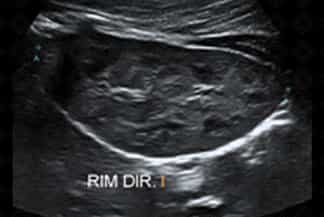

Texto alternativo para a imagem Figuras 1, 2, 3 e 4. Créditos: Dra. Elazir Mota - Rio de Janeiro/RJ

Descrição das figuras 1, 2, 3 e 4: Ultrassonografia das vias urinárias evidenciando rins em ferradura. Observe que o rim esquerdo é menor e apresenta alteração rotacional. Ao avaliar a linha média, anteriormente à aorta, observa-se a fusão dos polos renais inferiores.

• Ultrassonografia das vias urinárias: N ota-se fusão dos pólos inferiores dos rins na linha média, anteriormente à aorta (como nas imagens radiológicas). Sempre avaliar bexiga e sistema coletor, buscando por sinais de dilatação, já que nestes casos é comum a dificuldade de drenagem nas pelves renais;